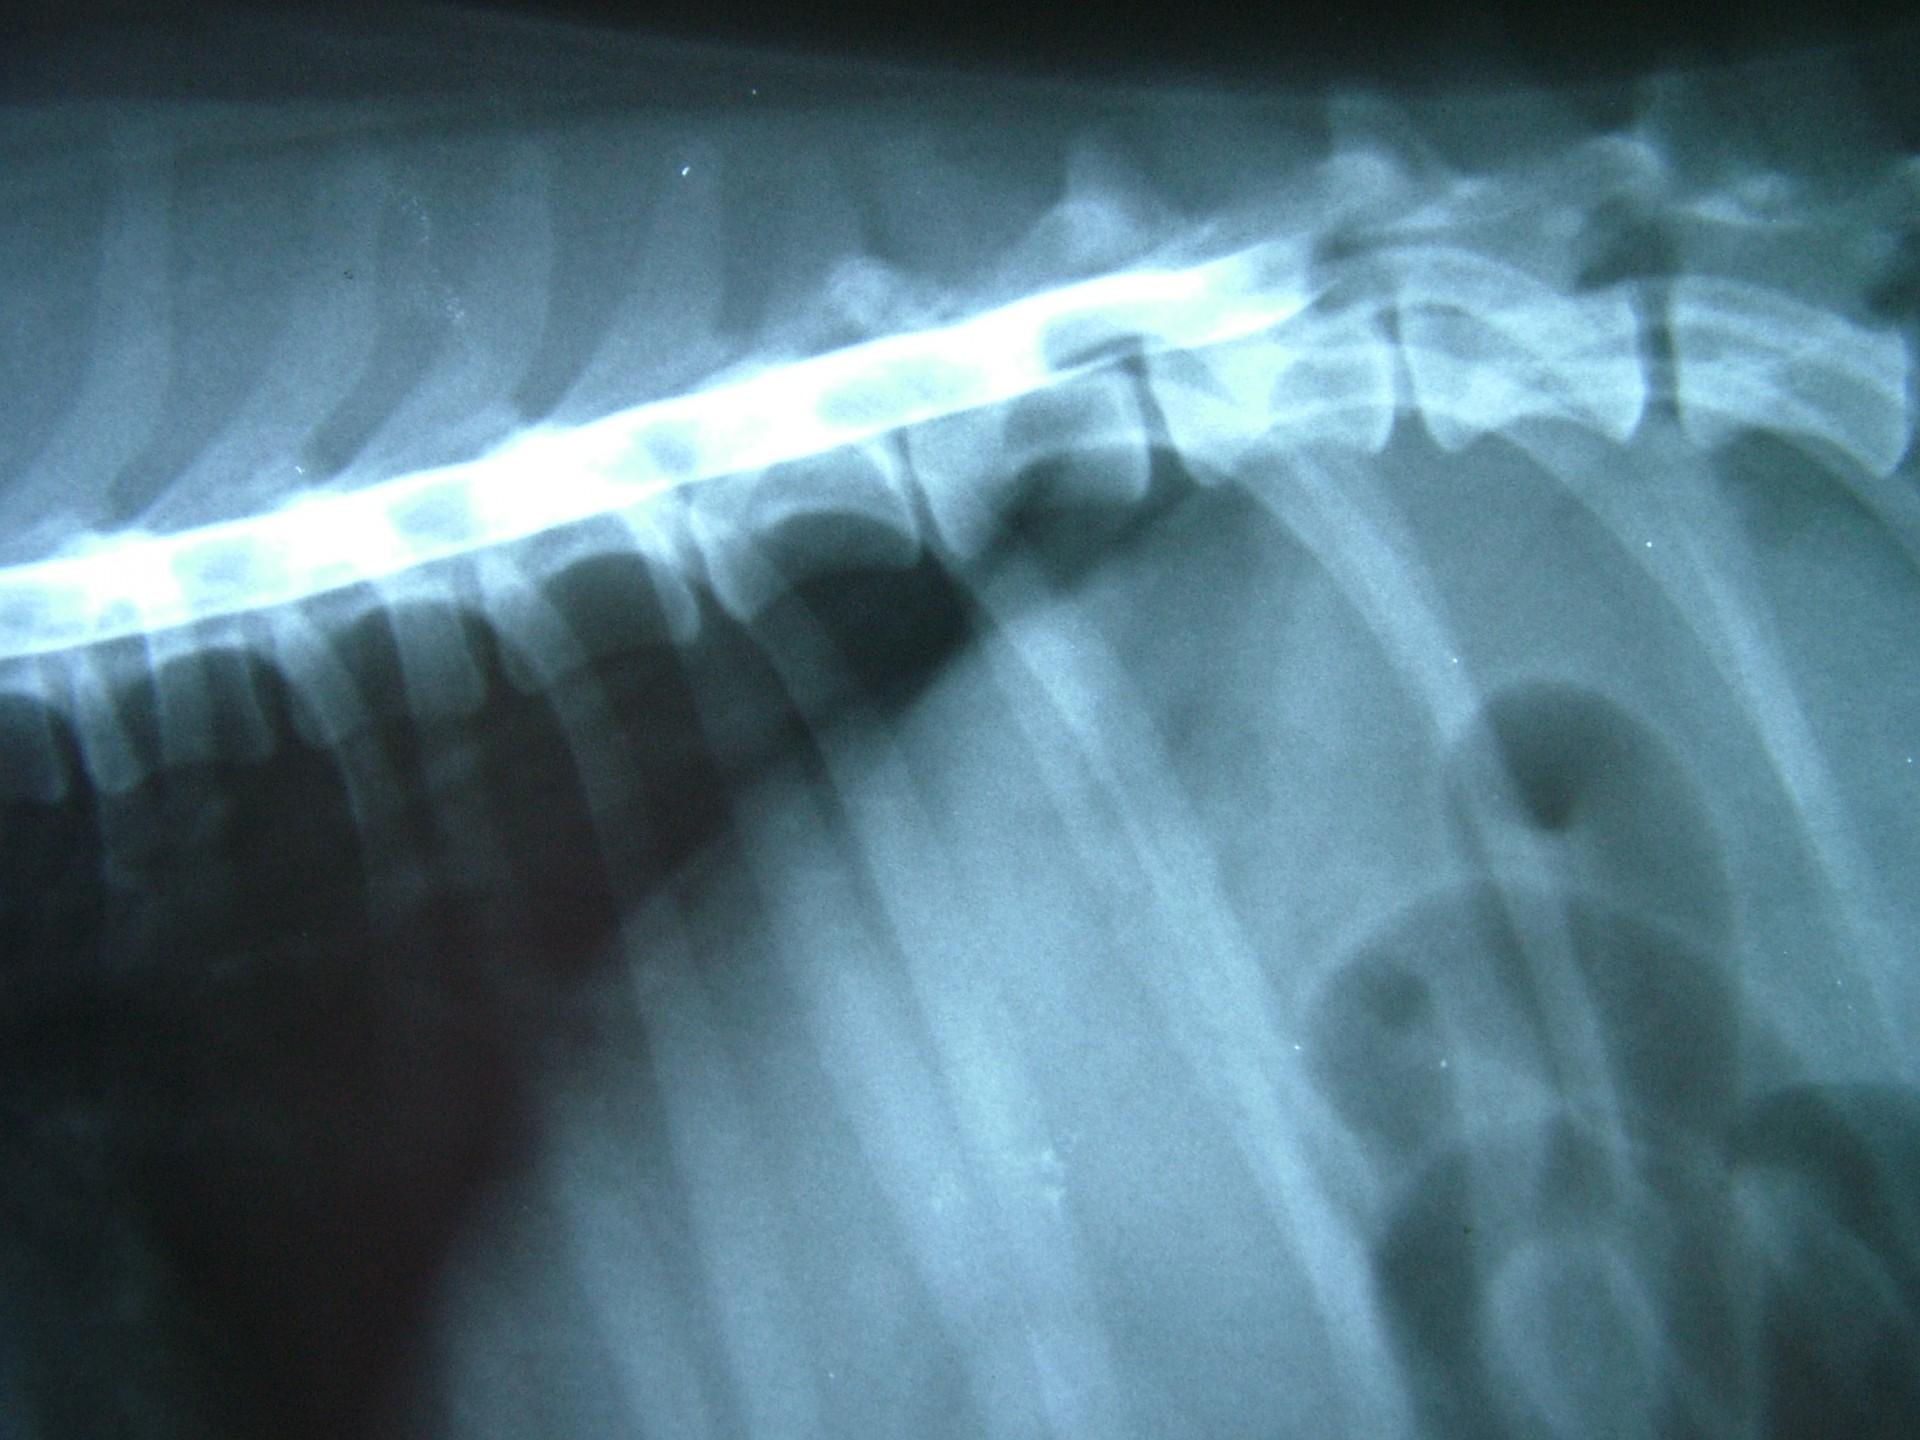

Az alapos neurológiai vizsgálattal és natív röntgen felvétel készítésével ugyan a gerincvelő sérülésének helye megjósolható, a porckorongsérv pontos lokalizációjának meghatározásához kiegészítő vizsgálatra, a gerinccsatorna megfestésére (myelographia) vagy egyéb képalkotó vizsgálatra (CT, MRI) van szükség.

A myelographia során egy, a röntgen felvételen látható kontrasztanyagot juttatunk a gerinccsatornába, pontosan a gerincvelő és az azt körülvevő un.: kemény gerincburok (dura mater) közé. Ezt követően az állatot kb.: 45°-os szögben egy erre alkalmas asztalon lógatjuk, így a kontrasztanyag addig folyik a gerinccsatornában, amíg a gerincvelőt összenyomó porckoronghoz ér. Az így készített RTG felvételen az összenyomatást okozó előesett porckorong helye egyértelműen, az oldaldetermináció pedig általában meghatározható.A myelographia nagy előnye, hogy a betegvizsgálat helyén, azonnal elvégezhető, hátránya, hogy az altatásban történő vizsgálat invazív beavatkozás, mely után különféle szövődmények alakulhatnak ki.